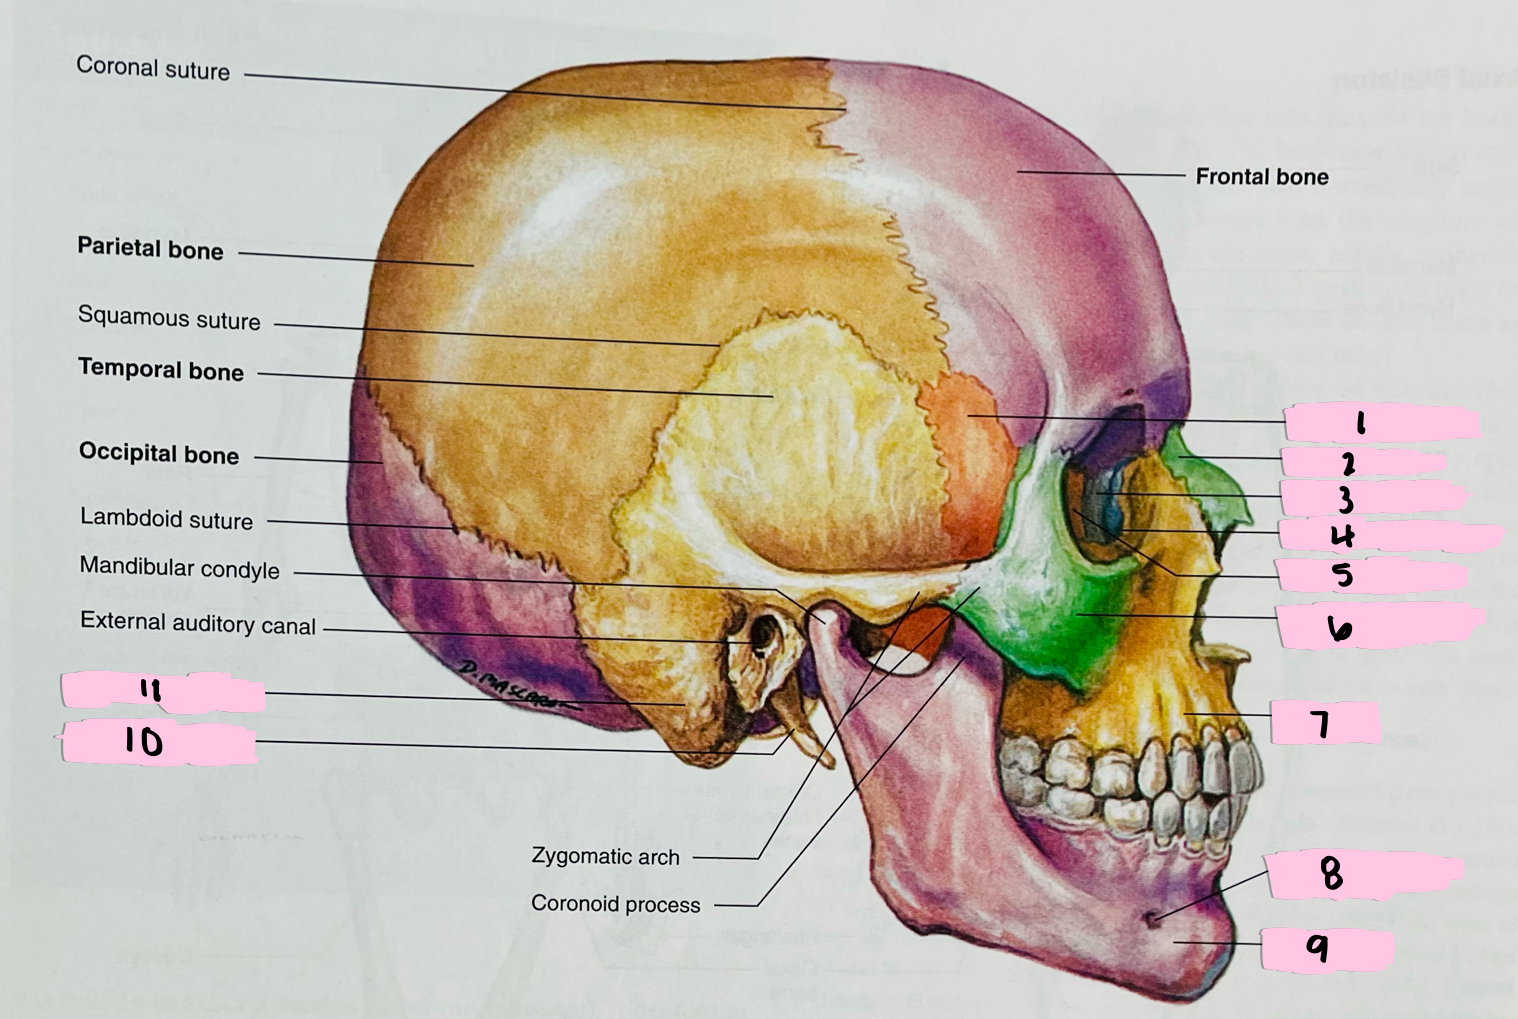

What is 1 pointing to?

Sphenoid bone

What is 2 pointing to?

Nasal bone

What is 3 pointing to?

Lacrimal bone

What is 4 pointing to?

Nasolacrimal canal

What is 5 pointing to?

Ethmoid bone

What is 6 pointing to?

Zygomatic bone

What is 7 pointing to?

Maxilla

What is 8 pointing to?

Mental foramen

What is 9 pointing to?

Mandible

What is 10 pointing to?

Styloid process

What is 11 pointing to?

Mastoid process